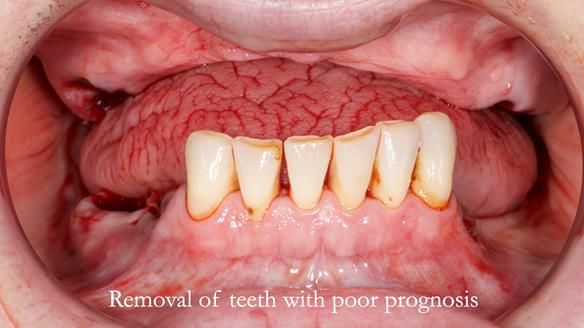

- The upper natural teeth have hopeless prognosis due to dental caries.

- The LR6, 5, 4 have guarded prognosis because of dental caries.

- The lower front teeth (LR3 – LL3) have better prognosis (although, I think there is high chance of loss – over the next 10 - 15 years). However, I do not believe it is right to remove them as they are in good condition compared with the other teeth and coping with a lower full denture is far more difficult (affecting your quality of life) than a lower metal based partial denture supported by natural teeth as proposed in the treatment plan below.

- Upper complete denture and lower partial denture along with removal of failing teeth - Jo wanted this

The clinical situation and treatment process is shown in detail below. I provided the clinical work. Rowan Garstang provided the technical work. This treatment took 25 visits over a period of 12 months.